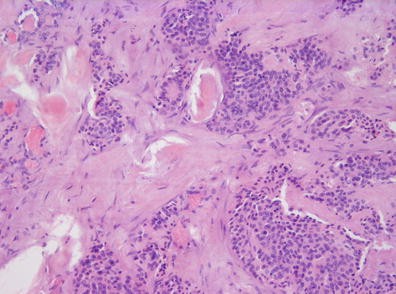

Objective: The aim of the study was to investigate Cellular Retinoic Acid Binding protein type I (CRABP I) expression and its clinical significance in pancreatic neuroendocrine tumors (pNETs).

Method: Protein expression of CRABP I was investigated by immunohistochemical analysis in 71 pNETs of various histological subtypes, including well- and poorly differentiated neuroendocrine neoplasms. Relationship of CRABP I expression to clinical and pathological features, grading and cell proliferation (index Ki-67) was analyzed.

Results: Increased expression of CRABP I protein was detected in 43.7 % (31of 71) of cases, including 16.7 % (1 of 6), 42.1 % (24 of 57) and 75.0 % (6 of 8) of pNET G1, pNET G2 and pNEC G3, respectively. We found the significant relationship of increased CRABP I expression to histological differentiation (p = 0.003), primary tumor size (p = 0.024), lymph node and liver metastases (p = 0.017 and p = 0.024, respectively) and cell proliferation, evaluated on the basis of the Ki-67(MIB-1) antigen expression (p = 0.000). The protein expression was not associated with outcome and survival of pNET patients.

Conclusion: The increased protein expression and association with high-risk factors suggest the great potential prognostic and therapeutic interest of evaluation of CRABP I in pNETs. Further study is necessary to clarify the role of CRABP I protein in pNET pathogenesis.

CRABP I expression in the cell cytoplasm of pNET G2 (Ki-67–9 %).: